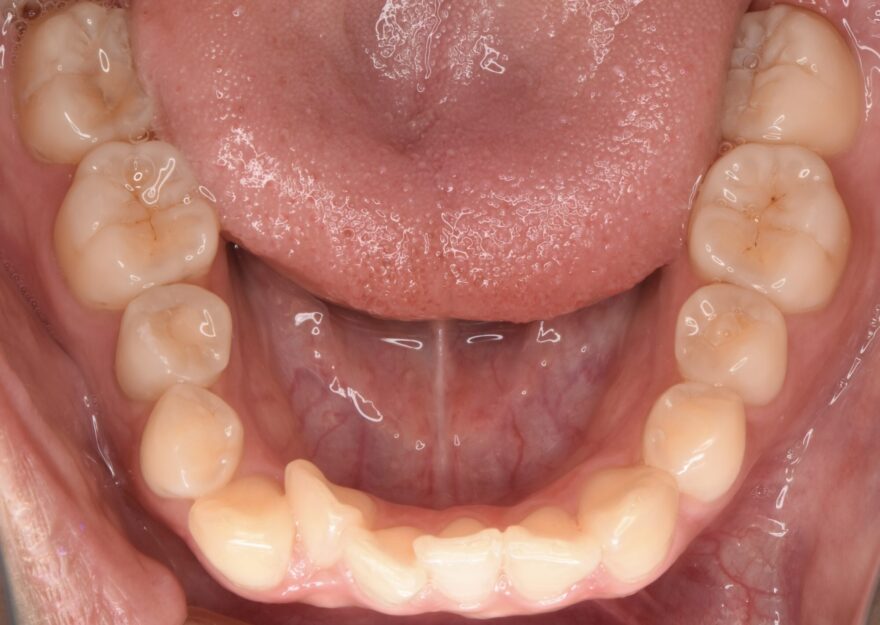

初診時の口腔内写真

前歯が捻じれてしまっています。

側方から見ると、前歯が90度以上回転していることがわかります。

最後方の奥歯が噛んでいません。